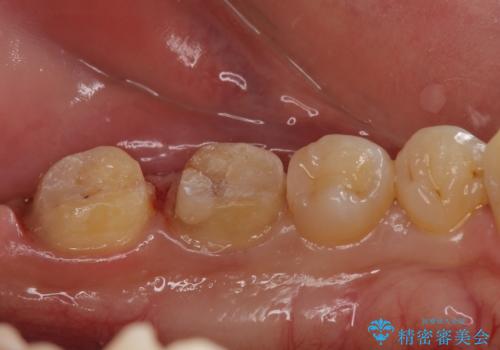

放置した虫歯の治療 親知らずの手前が虫歯

- 詰め物が取れて放置していたとのこと。

虫歯が大きかったため、被せ物(クラウン)としました。

親知らずを抜いてから治療しています。

- 22万円 (左下67 仮歯1万円x2 ジルコニアクラウン10万円x2)費用は治療当時の料金となります

幸い神経を取らずにすみました。